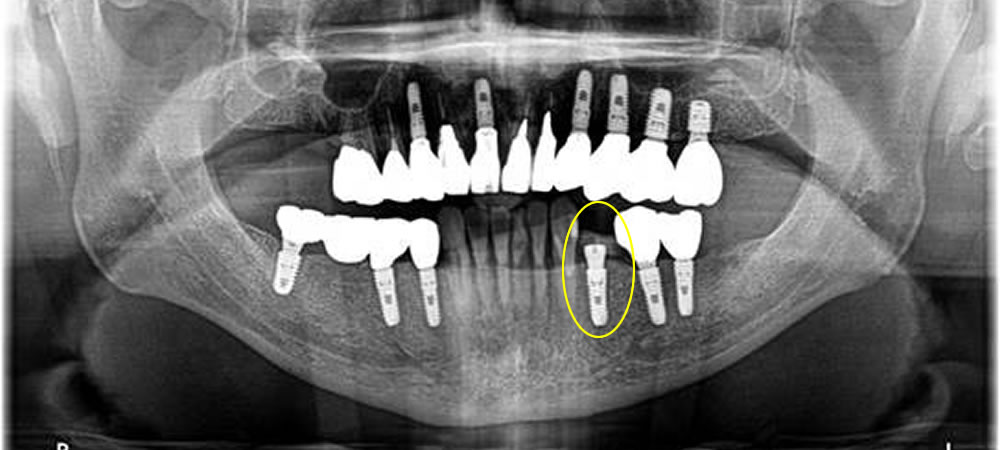

歯科用CT(三次元画像診断装置)

歯科用CTはお口の中や顎の骨の状態を、断層撮影によって三次元の立体画像として捉えることができる、現代の精密歯科治療に欠かせない診断装置です。 従来の二次元的なレントゲン写真では把握することが不可能だった、顎の骨の厚みや密度、内部を走行する神経や血管の正確な位置関係、歯の根の複雑な形態や病巣の広がりなどを、あらゆる角度から詳細に観察・分析することができます。 これにより、より安全で確実な治療計画の立案が可能となります。

インプラント治療における安全性と確実性を高める

インプラントを顎の骨に埋め込む際には、骨の中にある重要な神経や血管を絶対に損傷させないことが、安全な手術の大前提です。 CTによる三次元的な術前シミュレーションを行うことで、インプラントを埋め込む最適な位置、角度、深さを0.1ミリ単位の精度で計画することができ、手術のリスクを限りなく低減させます。 骨の量が不足しているいわゆる難症例においても、骨造成術の必要性や適切な術式を判断するための、客観的で信頼性の高い情報を提供します。